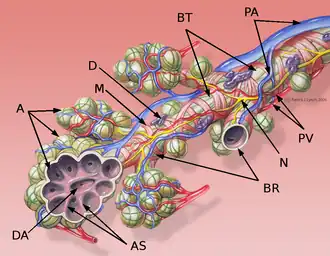

En cada lóbulo se distinguen diferentes segmentos, bien diferenciados, correspondiéndole a cada uno un bronquio segmentario (3.ª generación bronquial). Existen varias clasificaciones para nombrar a los diferentes segmentos, siendo una de las más aceptadas la de Boyden.[2] Los bronquios segmentarios se subdividen en bronquios propiamente dichos y bronquiolos (generaciones 12-16). Estos últimos carecen de cartílago y se ramifican en bronquiolos terminales y bronquiolos respiratorios (generaciones 17 a 19) que desembocan en los alvéolos: las unidades funcionantes de intercambio gaseoso del pulmón.

Circulación

El pulmón recibe la sangre procedente del ventrículo derecho a través de la arteria pulmonar. La arteria pulmonar se divide en dos ramas una para el pulmón derecho y otra para el izquierdo, las cuales se ramifican progresivamente siguiendo un trayecto paralelo al de las vías respiratorias. El sistema venoso es más variable y puede disponerse en diferentes trayectos, pero finalmente las cuatro venas pulmonares, dos procedentes del pulmón derecho y dos del izquierdo, desembocan en la aurícula izquierda. Hay que tener en cuenta que la circulación pulmonar presenta una peculiaridad con respecto al resto de la circulación sistémica, puesto que las arterias pulmonares son las únicas arterias del organismo que transportan sangre desoxigenada, mientras que las venas pulmonares, tras el intercambio gaseoso en los alvéolos, aportan sangre oxigenada hacia la aurícula izquierda, el intercambio entre oxígeno y dióxido de carbono se realiza mediante difusión entre la luz de los alveolos pulmonares y los capilares sanguíneos.[4]

Por otra parte el pulmón recibe sangre oxigenada a través de las arterias bronquiales que surgen directamente de la arteria aorta, esta sangre oxigenada irriga sobre todo las paredes de los bronquios y los bronquiolos.[4]